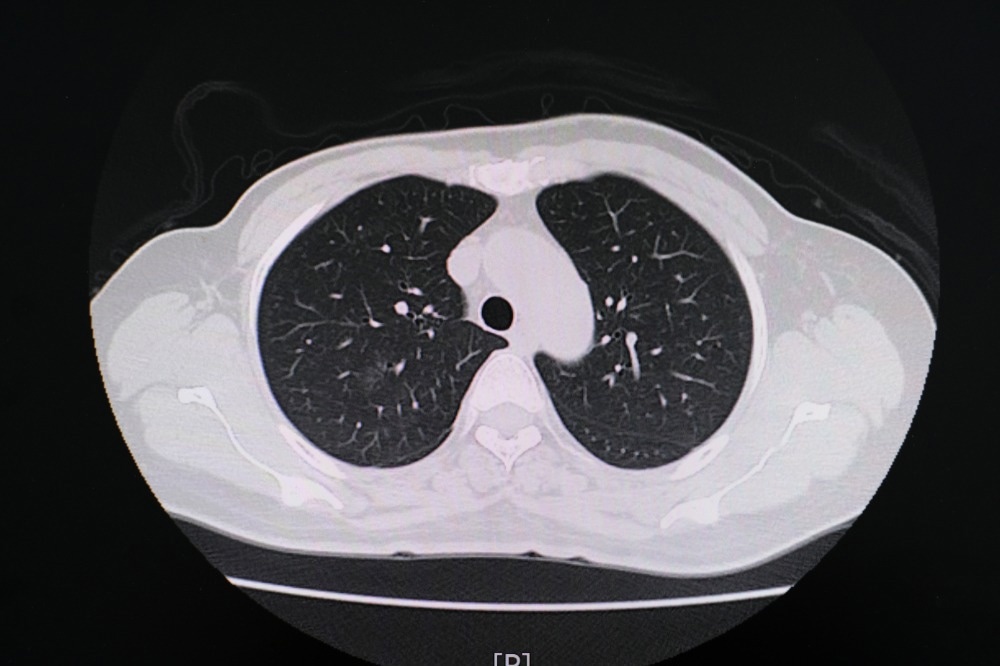

Study: Chest CT Findings in Marijuana Smokers. Image Credit: PIJITRA PHOMKHAM / Shutterstock.com

In a recent Radiology journal study, researchers report chest computed tomography (CT) findings that the lungs of marijuana smokers exhibit more significant levels of airway inflammatory markers and emphysema as compared to those of tobacco-only smokers.